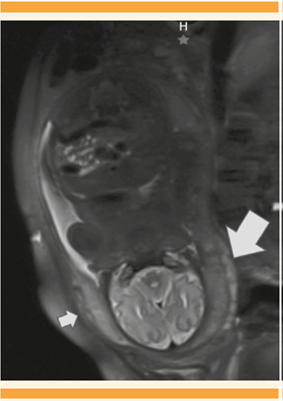

La resonancia magnética documentó, nuevamente, placenta subcenturiata y acretismo placentario sin datos de invasión a la vejiga. Figura 4

Figura 4 Placenta subcenturiata con lóbulo mayor posterior (flecha grande) y lóbulo menor en la parte anterior (flecha pequeña) en donde se sugiere acretismo placentario.